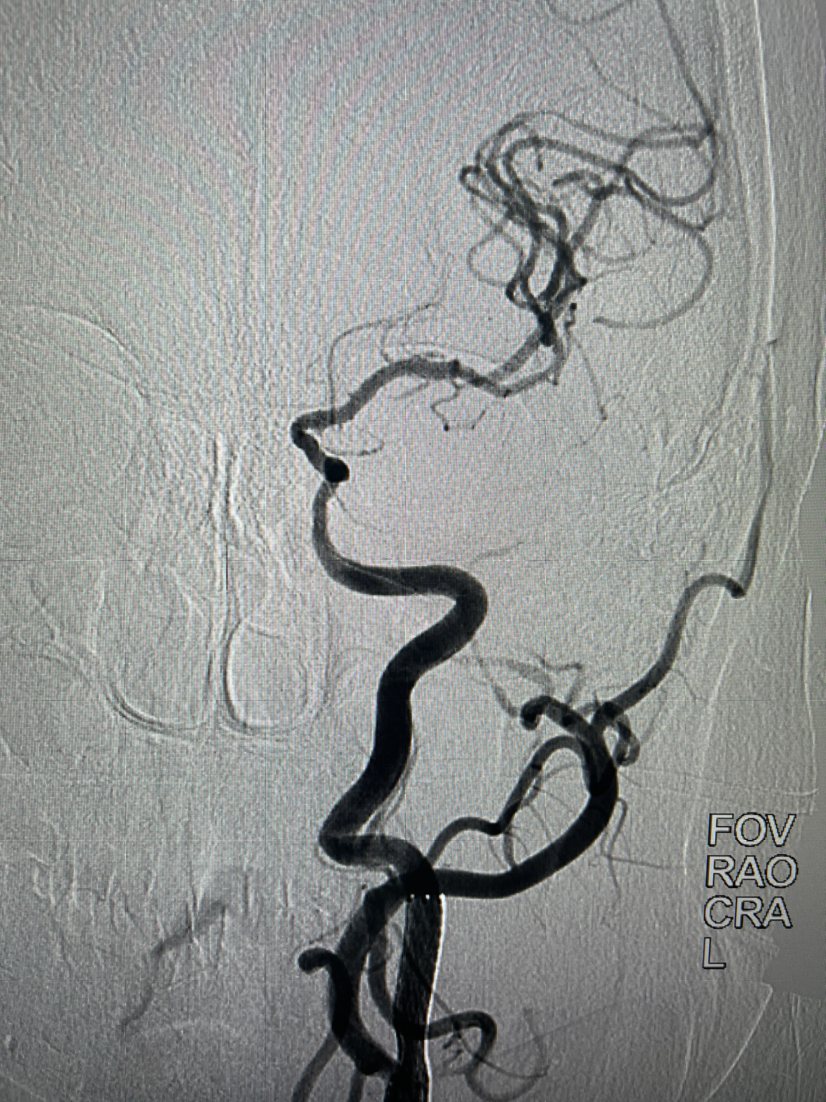

颈内动脉正位造影左侧大脑前动脉缺如

颈内动脉侧位起始部重度狭窄,大脑中M2重度狭窄